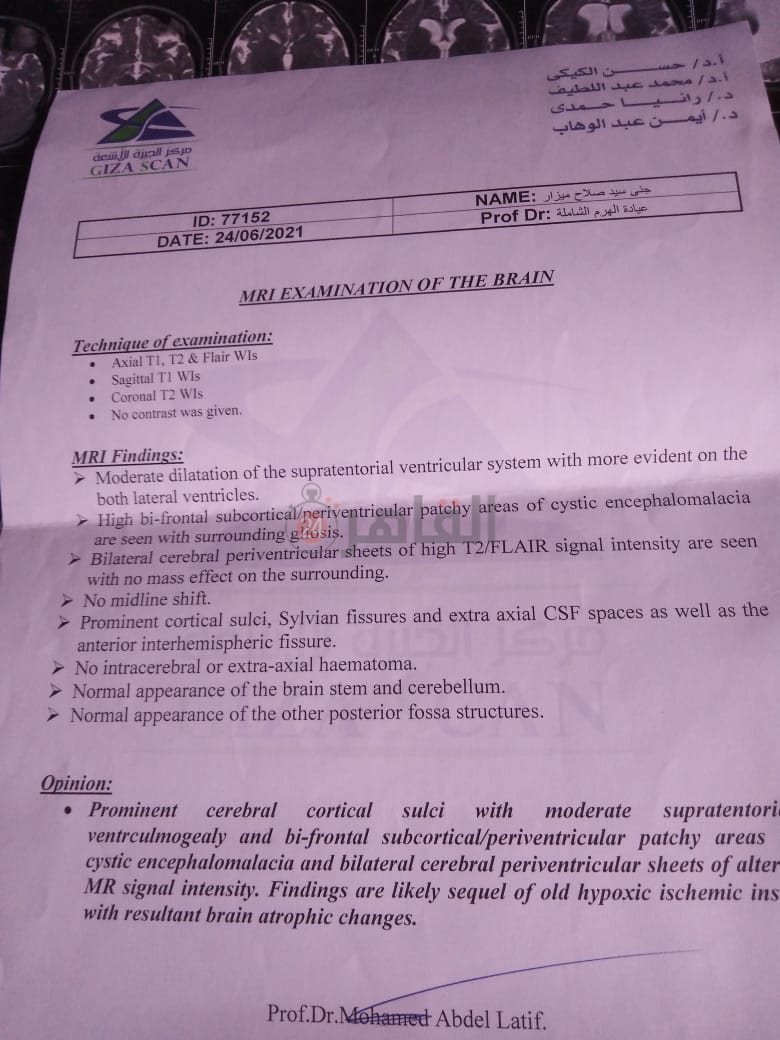

من جانبه، قال صلاح سيد، والد الطفلة جنى صلاح، إن ابنته تعاني من ضمور في المخ منذ ولادتها، نتيجة خطأ طبي، أدى إلى نقص كبير في الأكسجين لديها.

وأضاف في تصريحات خاصة لـ "القاهرة 24": "جنى تبلغ من العمر 6 سنوات، لا تستطيع المشي أو الوقوف على قدميها، نتيجة إصابتها بضمور في المخ منذ ولادتها".

وتابع: "مكنتش بتتحرك خالص، وجسمها طري، روحت كشفت عليها، وعملت أشعة وتحاليل كتير، أتأكدنا إصابتها بضمور في المخ"، مضيفًا:" مش بتعرف تأكل احنا اللي بنأكلها، هي عقلها كويس لكن مش بتتحرك ولا تتكلم".

وأوضح أن الطبيب الخاص بها أكد أن هناك داء خارج مصر يحسن من حالتها، ولكن باهظ الثمن، وتحتاج تناوله بشكل دوري.